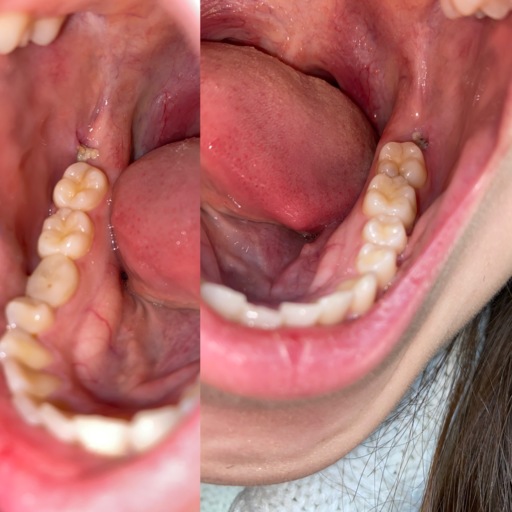

Hi, I have a frenulum on the right side of my mouth. It connects to my gums about 1cm behind the upper and lower back molars. It has become tight and painful. Have you ever seen anything like this? Is it safe to have it cut? I will attempt to add a photo. Thank you, H. Jay Graber

A frenum or frenulum is a small fold of tissue that restricts and secures the motion of a mobile organ.  I have not heard of a frenulum in the back of the mouth. It would be best to bring this to the attention of your dentist, especially because it is causing discomfort.  I did not see a picture attached to your question, however I am wondering if it is part of your cheek or possibly an impacted tooth that may be causing this discomfort.  Use warm salt water rinses several times a day to soothe the tissues until you have a proper exam and diagnosis.

A frenulum or frenum is a small fold of tissue that restricts or secures the motion of a mobile organ.  I have not seen a fold of tissue (unless sutured) that connects distal to the molars.  There is a frenum that connects your tongue to the floor of your mouth as well as one that attaches your lips to your jaws.  Since you are experiencing pain, it is important for you to see your dentist immediately to be sure you do not have an infection or a tooth that is creating swelling in the area.